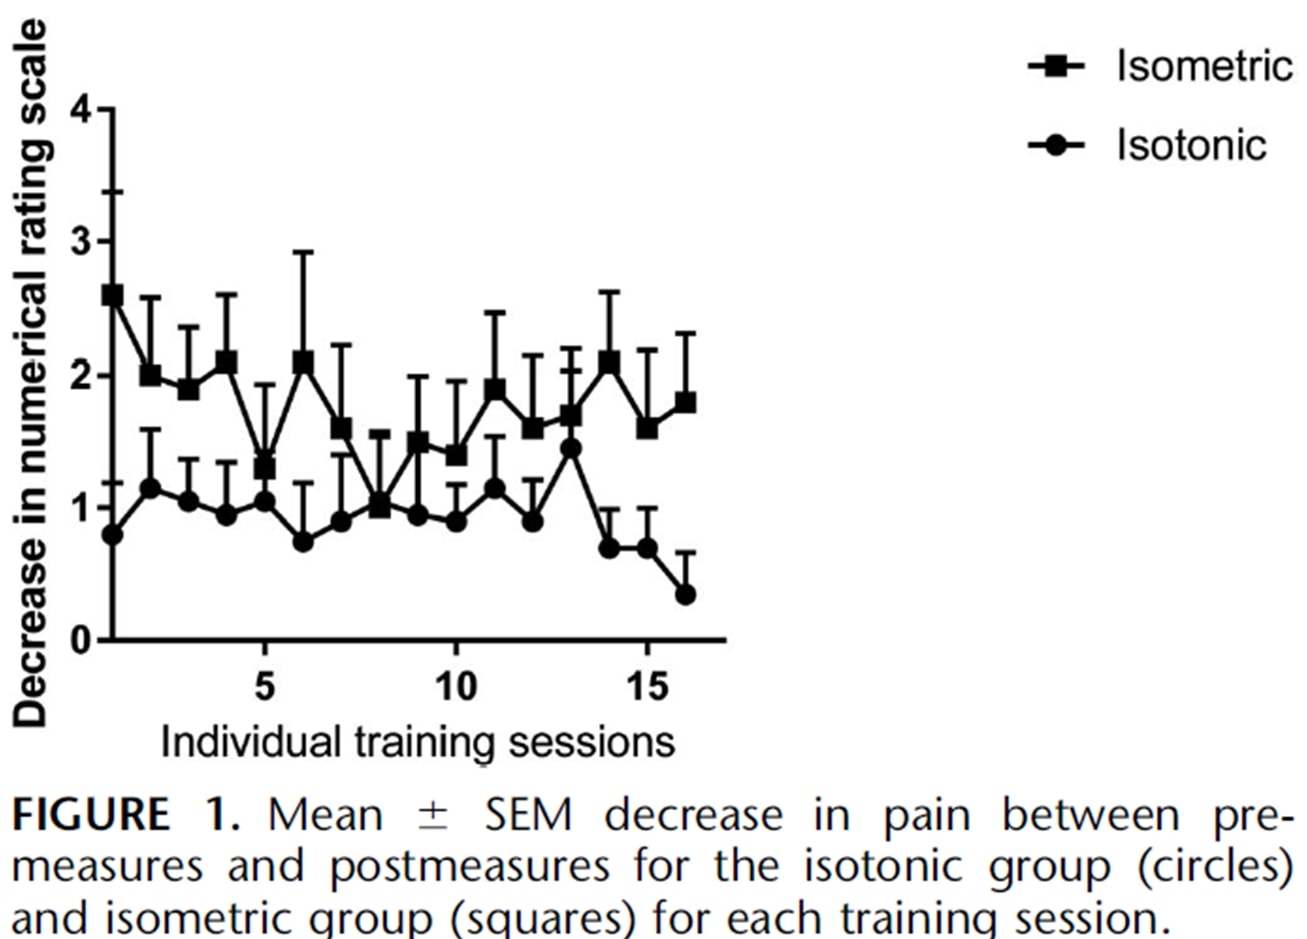

Gli stessi autori hanno condotto uno studio di follow-up sulla stagione con atleti saltatori due anni dopo (Rio et al. 2017) in cui hanno confrontato un programma isometrico e uno isotonico. In questo studio i risultati sono stati un po' più eterogenei in entrambi i gruppi, con una maggiore riduzione immediata del dolore nel gruppo isometrico:

Un recente studio di Holden et al. (2019) ha esaminato l'effetto dell'isometria anche nella tendinopatia rotulea e non ha riscontrato alcun effetto analgesico:

Figura tratta da Holden et al. (2019)

Tuttavia, l'alta percentuale di donne e l'età media relativamente alta sono atipiche per la tendinopatia rotulea, che di solito è una malattia dei giovani saltatori. Pertanto, è possibile che la diagnosi di tendinopatia rotulea non fosse corretta in alcuni casi. Sebbene questi due studi siano stati condotti sulla tendinopatia rotulea, vediamo se è possibile trasferire questi risultati ad altri tendini.